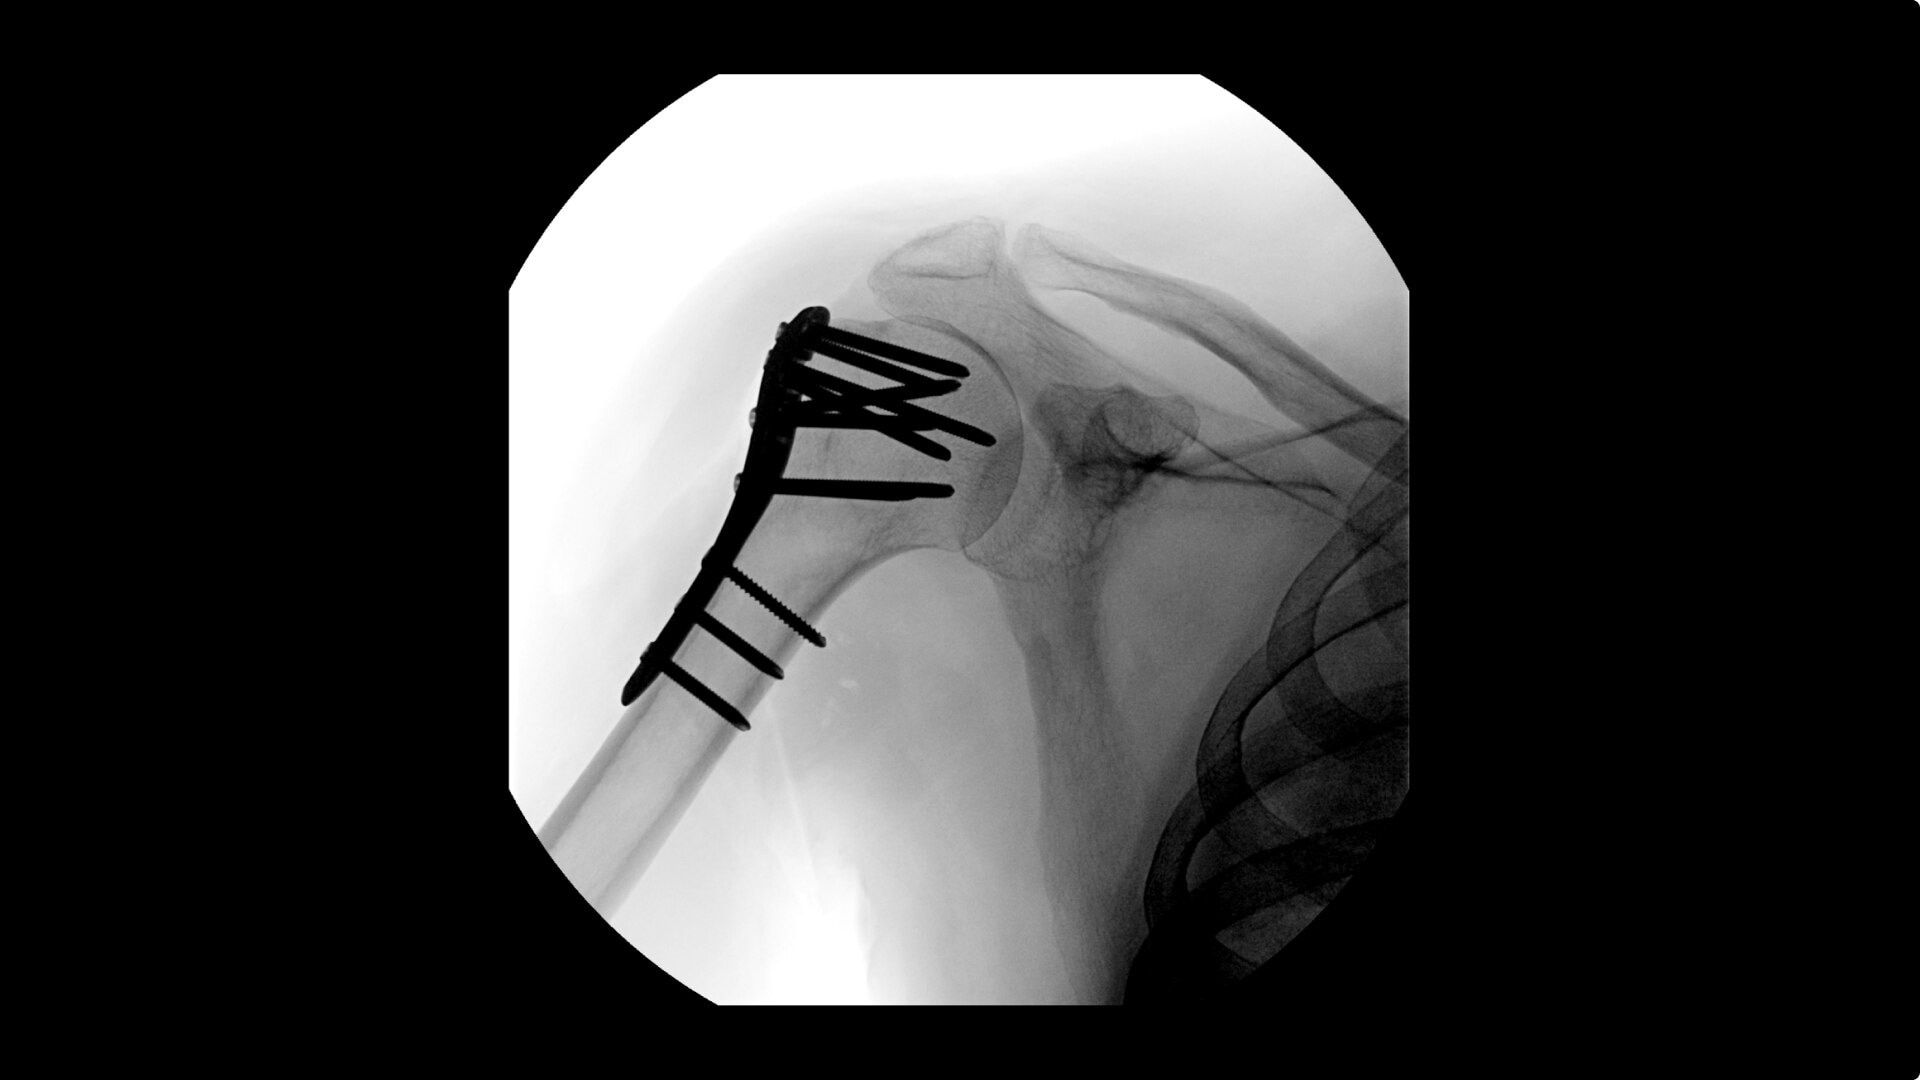

Complex orthopedic procedures require powerful imaging systems. OEC premium C-arms perform in a variety of procedures such as:

• Humeral fracture

• Shoulder fracture reduction